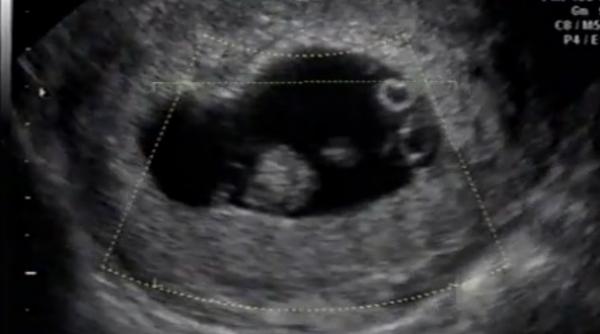

Șansele erau de 1 la 100 de milioane! Ce a născut o femeie din California a ULUIT lumea medicală (VIDEO)